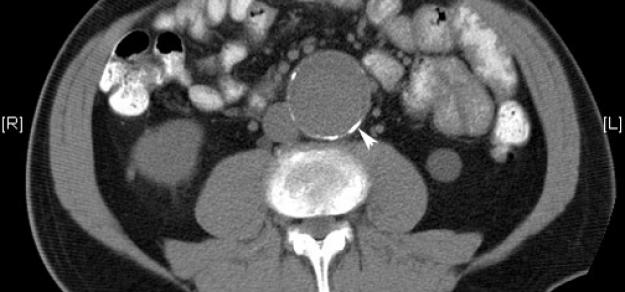

Prescripción de metformina y aneurisma aórtico

Heart, 1 de abril de 2019 la prescripción de metformina podría limitar la expansión de la AAA entre los pacientes con esta enfermedad, y podría estar involucrada con una menor incidencia de aneurisma aórtico y eventos de aneurisma aórtico